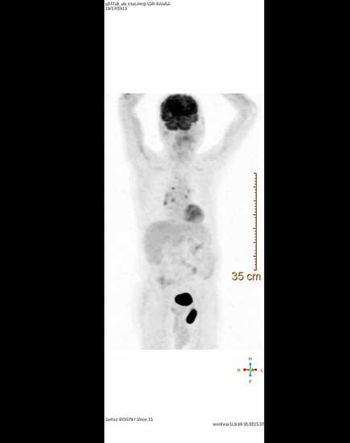

Case History: 40-year-old patient lump on left side of back.